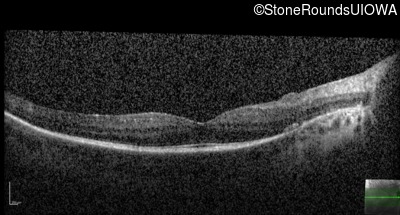

Optical Coherence Tomography - Left - 20/32

Exemplar / OCT Stack

OCT Stack